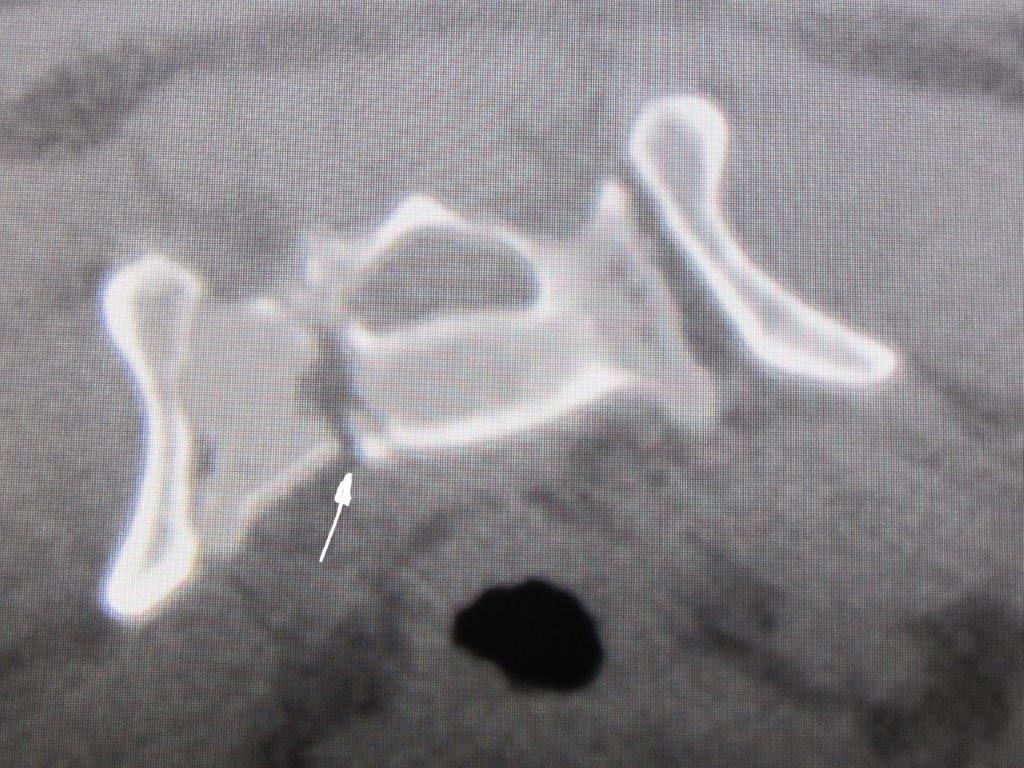

Wie auf dem Bild 3 dargestellt, zeigt sich am hinteren Rand des Acetabulum (Gelenkpfanne) ein kleines Knochenstück, das nur dezent verschoben ist. Die Gelenkpfanne ist im gesamten vorderen Teil der Gelenkfläche intakt.